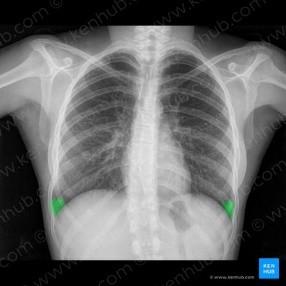

• Radiografía de tórax: índice cardiotorácico normal, hilios engrosados con adenopatías calcificadas. Silueta cardiomediastínica y parénquimas sin otros hallazgos.

Radiografía de tórax: índice cardiotorácico normal, hilios engrosados con adenopatías calcificadas. Silueta cardiomediastínica y parénquimas sin otros hallazgos.